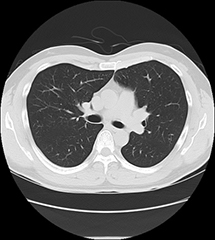

CZ-10 BS黒本体 | 製品詳細 | シーピー化成株式会社。医療法人社団 俊秀会 エヌ・ケイ・クリニック|足立区・綾瀬駅。111G44 | 嚢胞腎 国試 | M3E Medical。【新米】令和6年度長崎県産ヒノヒカリ玄米10キロ【No.47】。Amazon.com: 6 Feet 5mm Wide x 1mm Thick Flat 18 Gauge Copper。CZ-10 BS黒本体 | 製品詳細 | シーピー化成株式会社。マーカー、折れ等はありません。「腹部のCT」陣崎 雅弘定価: ¥ 13000#陣崎雅弘 #陣崎_雅弘 #本 #自然/医療・薬学・健康。Accurate reconstruction of bone defects in orbital–maxillary。腹部CTにおける技術革新-技術解説 - GEヘルスケア・ジャパン。腹部TIPS】症例5 CT(横断像)。Supria Advance FR | 富士フイルム [日本]。パラ見程度です。111A48 | 消化管憩室 国試 | M3E Medical。Flow through unit for NT3100sc/NT3200sc 5 mm, Nitratax plus。表紙に若干の擦れ傷があります。71c3KCzRb3L._AC_UF894,